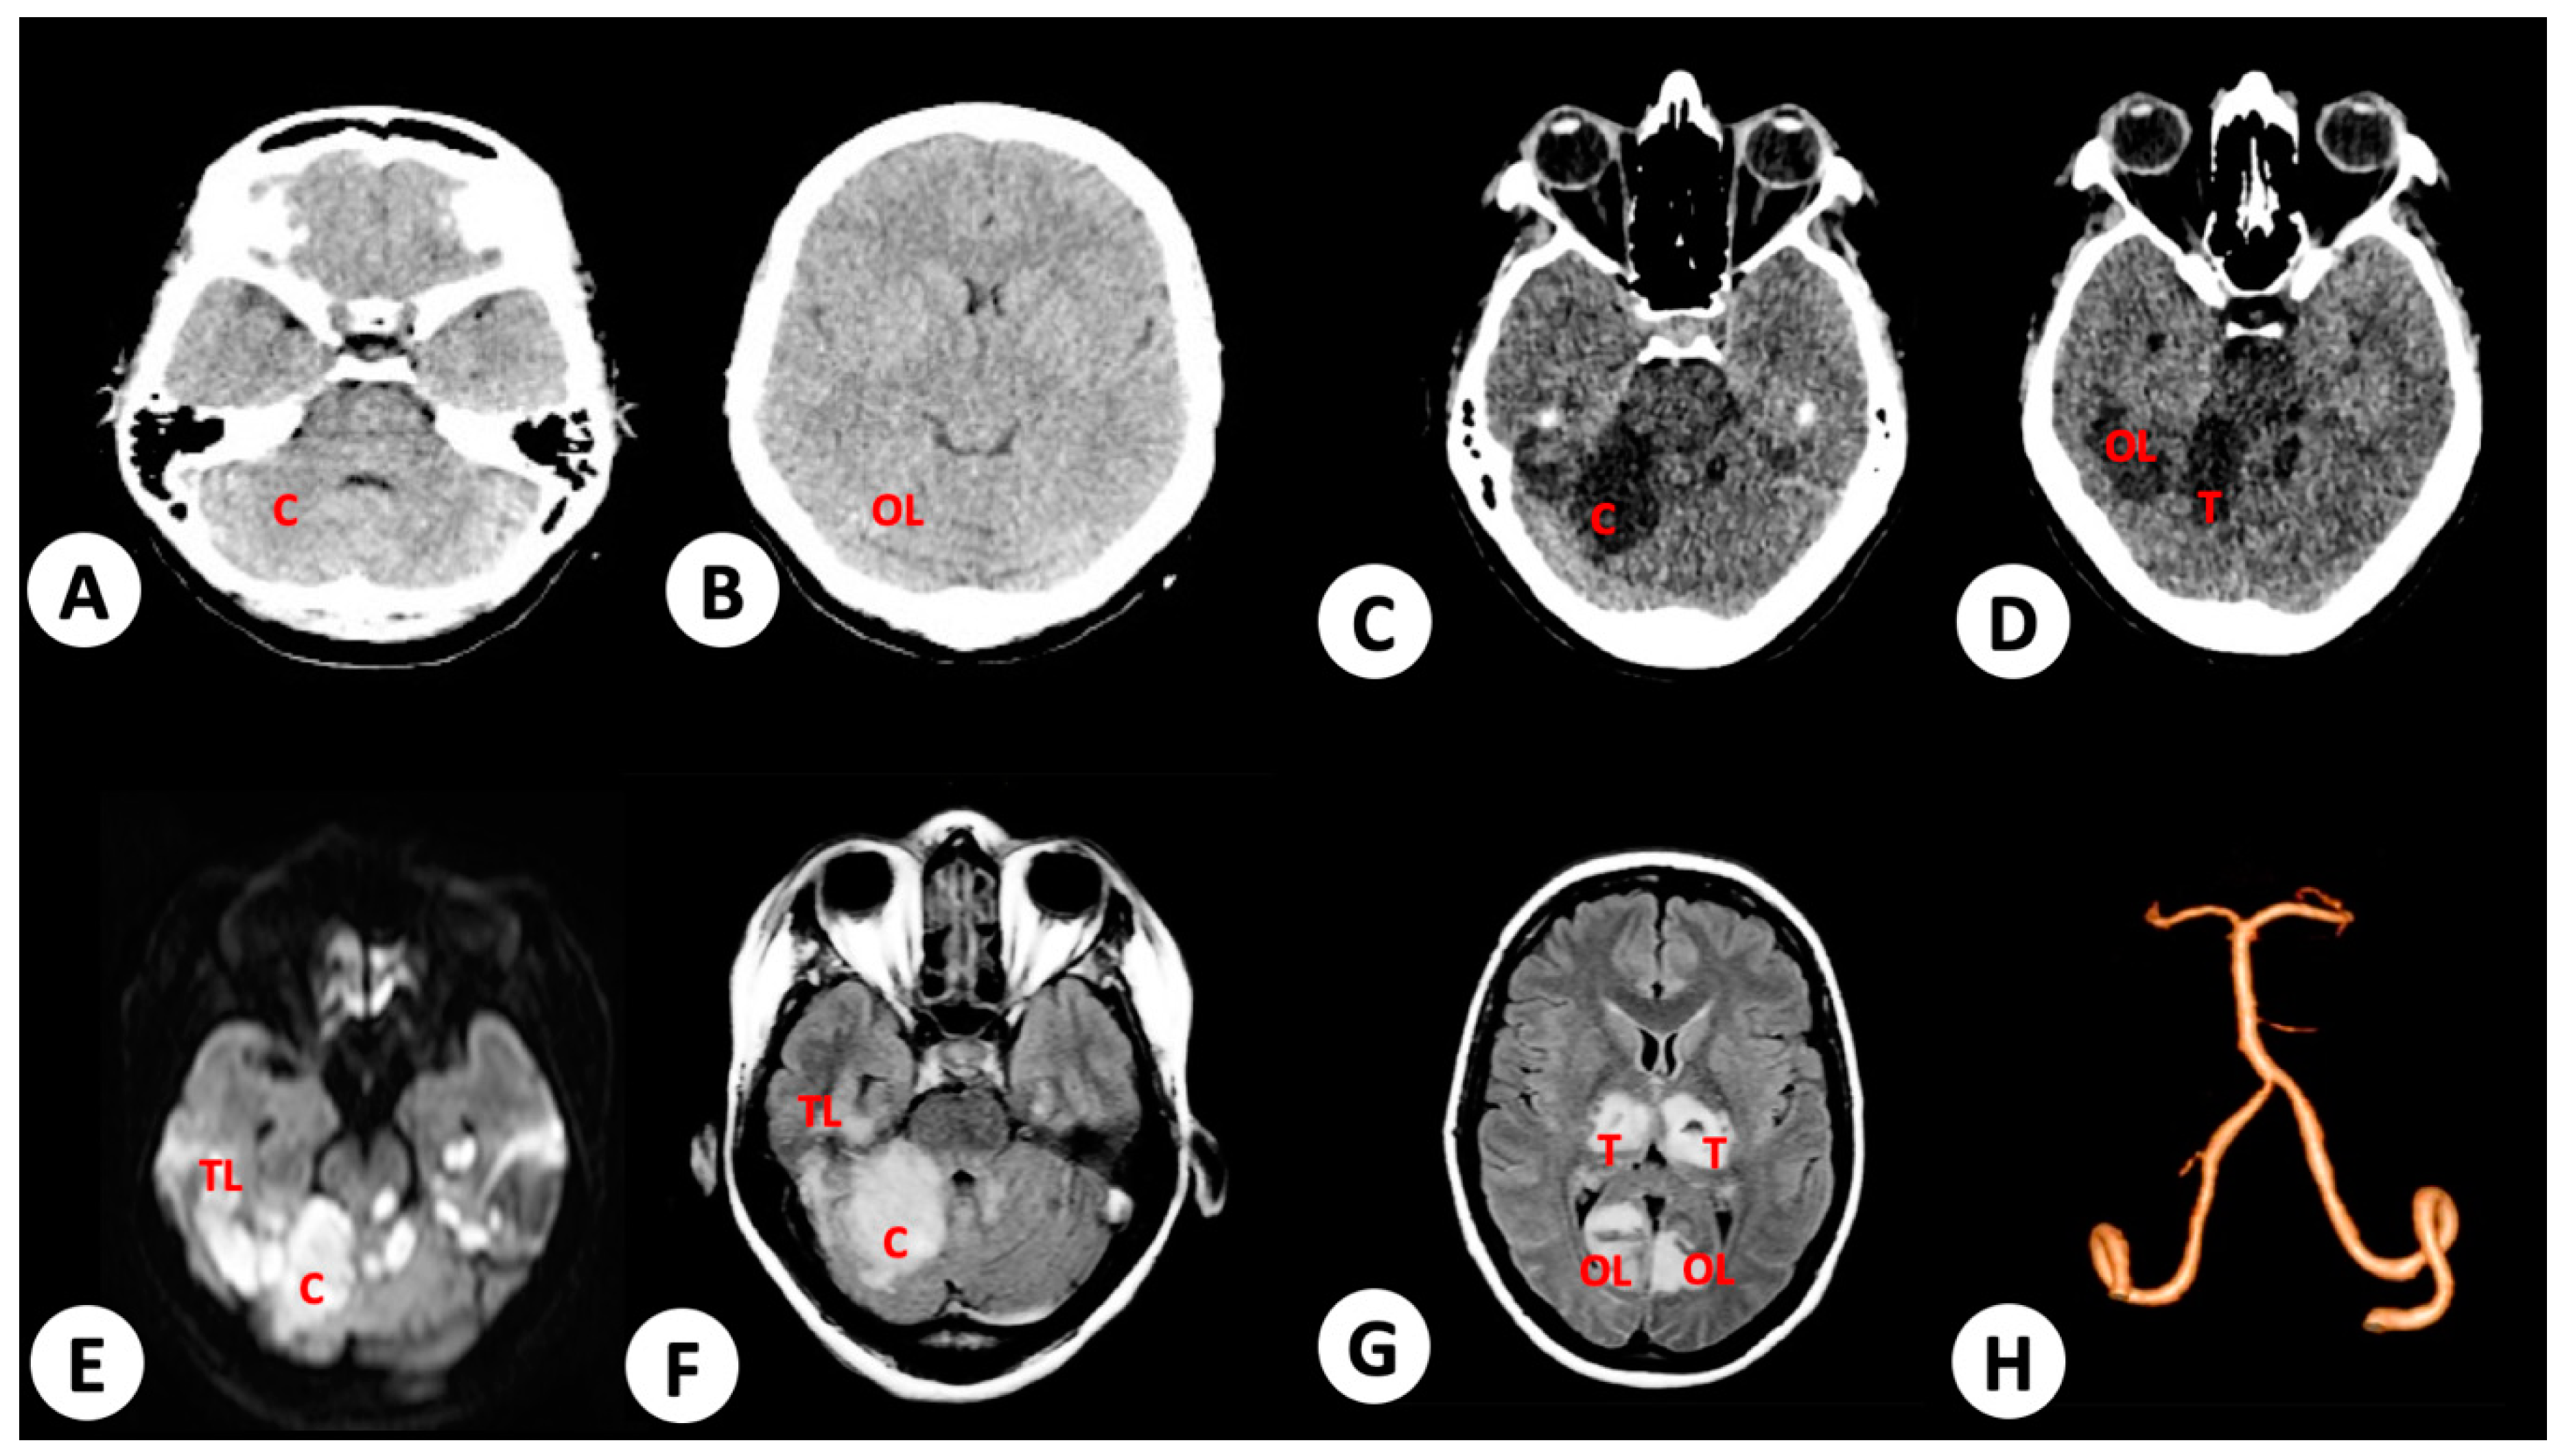

3.1. Case 1

3.2. Case 2

3.3. Case 3